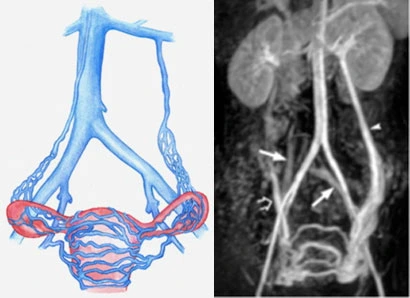

Il varicocele femminile, noto anche come varicocele pelvico, è una condizione poco conosciuta ma più comune di quanto si pensi. Si tratta di una dilatazione anomala delle vene nella zona pelvica, causata da un cattivo funzionamento delle valvole venose che impediscono al sangue di fluire correttamente. Questo ristagno di sangue provoca un aumento della pressione nelle vene, che si dilatano e possono causare fastidi persistenti o dolore cronico nella zona pelvica.

Spesso questa condizione è associata alla Sindrome da Congestione Pelvica (SCP), caratterizzata da un dolore pelvico cronico che dura da più di sei mesi. Il dolore può peggiorare dopo aver passato molto tempo in piedi, durante i rapporti sessuali o nel periodo premestruale, influenzando la qualità della vita.